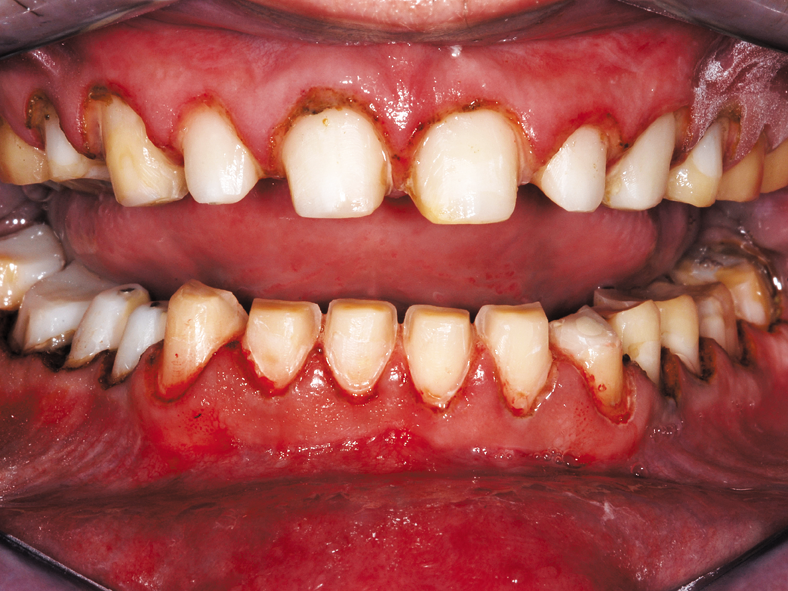

This clinical case demonstrates the use of CORE-FLO DC LITE with Bisco’s dual-cured UNIVERSAL PRIMER for post and core build-ups. The patient presented with advanced decay in multiple teeth. He was a relatively healthy 30-year-old male with a history of drug and alcohol abuse. He had recently completed a substance abuse rehabilitation program and wanted to finish his dental treatment.

He stopped his prior dental treatment while still in his temporary restorations. He eventually lost the temporaries and went without for several years. As a result he was left with extensive decay in the previously prepared anterior teeth (Figs. 1, 3).

He also had numerous areas of new decay in most of his remaining teeth, requiring a full mouth reconstruction. Our treatment plan was a 24 tooth reconstruction (missing first bicuspids) with root canal treatment for teeth #7-11 with fiber post build-ups using CORE-FLO DC LITE.